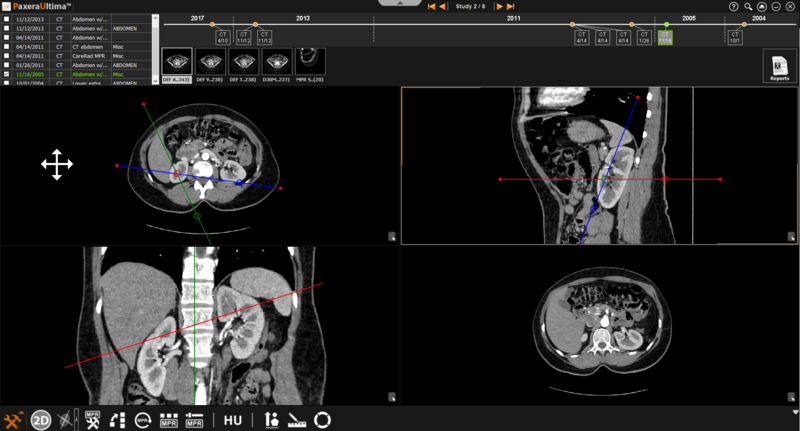

The bioblique MPR mode provides three planes (transverse, sagittal, and coronal) with lines that can rotate the angle of the planes. The image on the bottom right corner can be omitted within the bioblique mode.

» Adjust line position- The positions of the lines can be adjusted by clicking on the line of interest and dragging it in the direction of interest.

» Adjust line angle- The angle of the lines can be adjusted by clicking on the circle intercepting the line of interest and dragging it in the direction of interest.